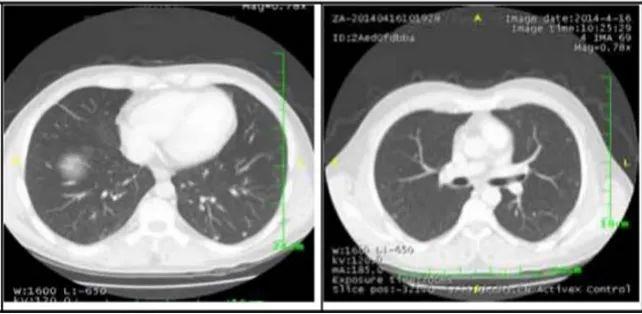

2. 肺部病灶治疗前后核磁对比:

肺部转移病灶在用药后2个月明显缩小,4个月后病灶基本消失。

治疗4个月

治疗6个月